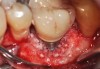

Clinical examination showed 2 mm of buccal recession with a shallow vestibule and absence of keratinized attached gingiva against the crown with 8 mm of circumferential pocketing accompanied by bleeding upon probing (Figure 15 and Figure 16). A periapical radiograph showed a symmetrical vertical osseous defect causing the loss of 50% of the bone around the implant (Figure 17). Because the patient had made a significant investment of time and finances to replace her lost tooth with the implant, she desired that the implant and restoration be retained, if feasible.

A surgical flap procedure was performed with the intent of thoroughly debriding the granulomatous tissue from the osseous defect (Figure 18 and Figure 19), mechanically and chemically detoxifying the surface of the implant (Figure 20 through Figure 22), and grafting the infrabony component of lesion with bone xenograft (Bio-Oss®, Geistlich Pharma, www.geistlich-na.com) in an attempt to reduce the vertical defect (Figure 23). To concurrently resolve the mucogingival problem, the plan called for placing a dermal allograft (Dermis Allograft, DENTSPLY International, www.dentsply.com) on the buccal (Figure 24) and then replacing the flap (Figure 25).

Fig 15. The implant-supported restoration of tooth No. 19 presented with a lack of attached keratinized gingiva, shallow buccal vestibule, and 2 mm of buccal recession.

Figure 15

Fig 16. The restoration exhibited an 8-mm pocket upon probing, with bleeding on the buccal aspect.

Figure 16

Fig 18. A full-thickness flap from teeth Nos. 18 to 20 revealed granulomatous tissue in the circumferential defect around implant No. 19.

Figure 18

Fig 19. The circumferential defect was debrided. Note excess cement extending apically from the margin of the crown into the defect; residual cement has been shown to be complicit in the development of peri-implant disease.

Figure 19